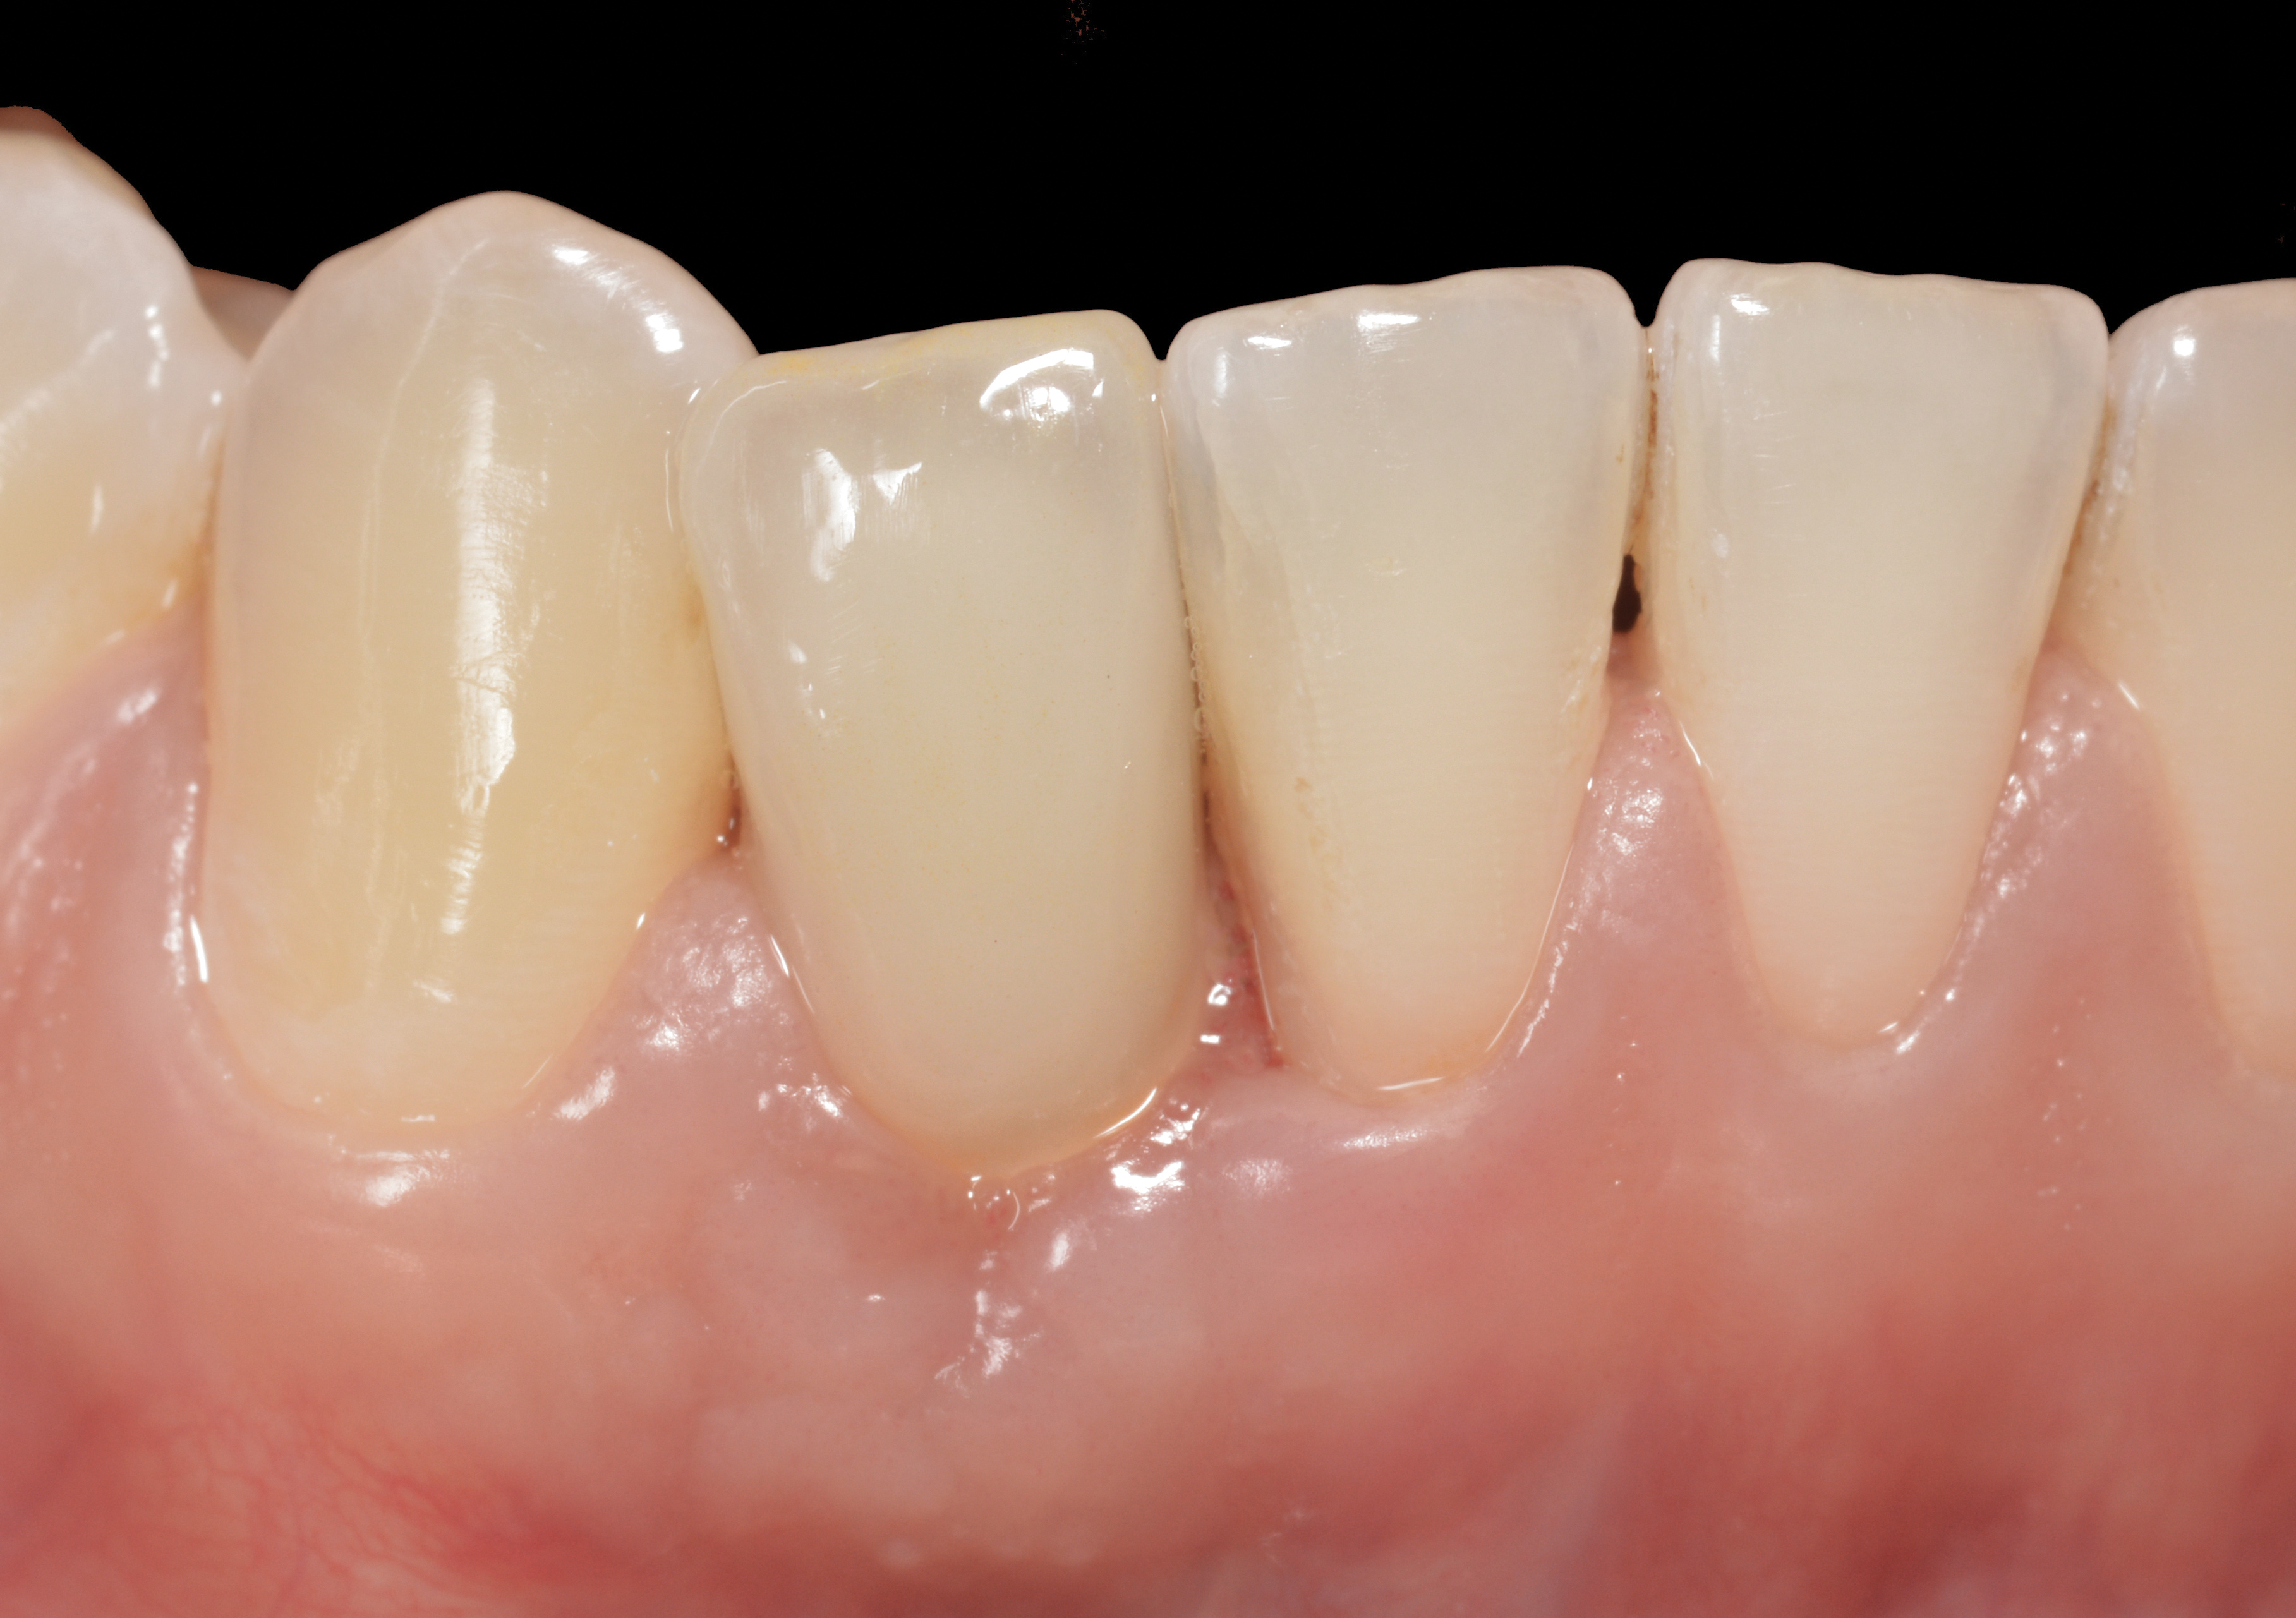

Fig 3. A patient presented with a high smile line and midfacial recession of the maxillary right lateral incisor as evidenced by the increased tooth length compared with the contralateral lateral incisor.

Figure 3

Fig 4. Intraoral view of tooth No. 7 with the gingival zenith more apical than the adjacent central incisor and canine tooth.

Figure 4

The following case report provides an example of this case scenario: A 28-year-old white female patient presented with her maxillary right lateral incisor significantly longer than the contralateral tooth following restoration of an existing crown that was 10 years old (Figure 3). The patient was dissatisfied with the esthetic appearance of the restoration due to the increased length, recession of the gingival tissues, and discoloration of the surrounding mucosa (Figure 4). Similar to case scenario No. 1, the first step in treatment was to decoronate the healthy implant by placing a flat surgical cover screw and employing a provisional resin-bonded-retained (RBR) prosthesis as a transitional fixed restoration (Figure 5 and Figure 6). The gingival augmentation in situ was allowed to take place for 2 to 3 weeks and was evaluated after that time (Figure 7).